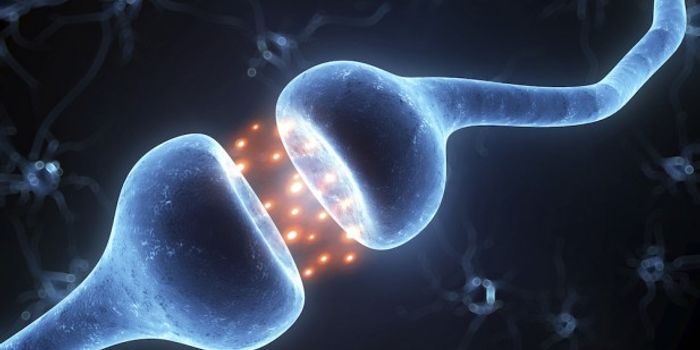

AUG 27, 2016Cell & Molecular BiologyNeurons signal to each other throughout the body using a connection called a synapse. While they are very small, they ar ...